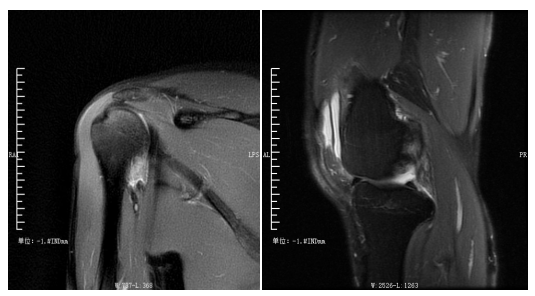

四肢关节:主要检查关节软骨、韧带、肌肉等病变。